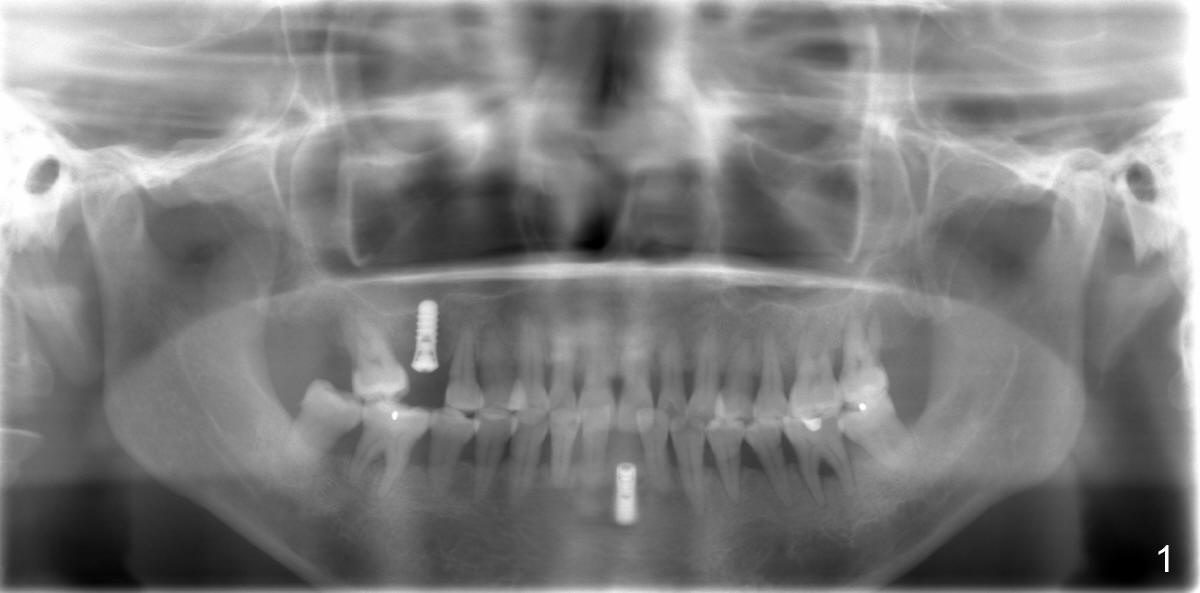

57岁 女性 中度牙周病 牙槽骨普遍中度吸收。(见全景片)

1,右上6上颌窦内提升2.5mm,植入4.1x10mm种植体,因右上7有近中倾斜并前移,5--7邻牙间距仅7.5mm,故选择了常规颈,包埋缝合。

2,左下1舌侧附着龈切口,翻开唇侧粘骨膜瓣,测量牙槽嵴唇舌侧厚度仅4mm,唇侧牙槽嵴下方明显凹陷,约厚3.5mm。证实了术前预估的骨量情况,如孔道唇侧侧壁穿孔就植骨粉,已和病人交待。